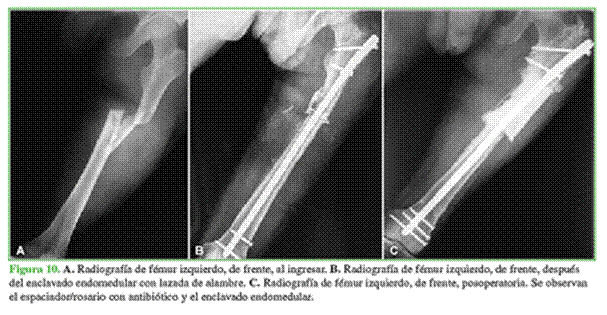

Hombre de 21 años, con una fractura diafisaria de fémur con exposición por la cara posterior del muslo que fue derivado a los cuatro días de sufrir un accidente automovilístico. Como antecedente se destaca la adicción a drogas. Inicialmente se realizó una limpieza mecánico-quirúrgica con colocación de tutor y revaluación a las 48 h. A los siete días, se efectuó un enclavado endomedular. Tres días después, fue dado de alta, sin complicaciones (Figura 10).

A los tres meses de la cirugía, el paciente acude por una secreción purulenta y una fístula que coincide con el sitio de exposición inicial en la cara posterior del muslo. Se realizaron dos limpiezas con rescate bacteriológico de S. aureus resistente a meticilina, y se indicó un tratamiento antibiótico dirigido. Ante la mala evolución se decidió retirar el material y colocar un nuevo clavo con recubrimiento antibiótico. El paciente se fugó del hospital y reingresó a los pocos días por una secreción de la herida. Se efectuó una nueva limpieza con rescate de Staphylococcus haemolyticus. Se indicó un tratamiento con psicología. Debido a la posibilidad de realizar un tratamiento antibiótico por vía oral, fue dado de alta con controles periódicos por consultorio externo. Al tercer mes, refirió que había abandonado el tratamiento antibiótico sin indicación médica y que no había concurrido a sesiones de kinesiología, tenía rigidez en la rodilla homolateral. El paciente no cumplió con las pautas traumatológicas e infectológicas y no se presentó a los controles posteriores. Al año del accidente, ingresa nuevamente con un absceso del muslo a tensión. En la radiografía, se observó una rarefacción del foco de fractura. Se realizaron dos nuevas limpiezas con rescate positivo para S. aureus sensible a meticilina. Debido a la mala evolución se optó por una conducta radical con retiro del implante, resección de fragmentos óseos de mal aspecto y colocación de espaciador de cemento con antibiótico. Ante la buena respuesta, fue dado de alta para terminar el tratamiento antibiótico en forma ambulatoria. Se solicitó una tomografía para la preparación del andamiaje a medida.

Una vez concluido el tratamiento antibiótico, se realizó una biopsia por punción con rescate negativo. Se procedió a la cirugía reconstructiva (Figura 11).